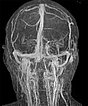

Koronare, kontrastmittelunterstützte, dynamische MR-Angiographie, MIP-Darstellung 33 s nach Injektion des Kontrastmittels. Die Darstellung hat bereits die venöse Phase erreicht, die venösen Blutleiter sind vollständig dargestellt. Die venöse Malformation selbst reichert zu diesem Zeitpunkt noch kein Kontrastmittel an.

Koronare, kontrastmittelunterstützte, dynamische MR-Angiographie, MIP-Darstellung 124 s nach Injektion des Kontrastmittels in der venösen Spätphase. Erst jetzt reichert die venöse Malformation langsam in Teilen etwas Kontrastmittel („pooling“) an.